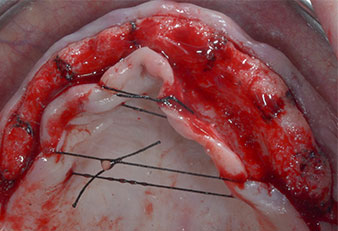

Three years later it was time for a maxillary denture of the same type. Based on CBCT planning sinus augmentation was avoided with the aid of short implants, and a surgical template was used to transfer the planned positions to the alveolar ridge (Figs. 1 and 2).

A flame-shaped, diamond-coated piezoelectric instrument (Piezomed I1) was used to mark the implant positions and to perform pilot preparation (Fig. 3). Care was taken to use an up and down movement, with reduced power, full irrigation and low pressure (below 300 g). Next a pilot instrument (Piezomed I2A/I2P) was applied for the initial 2 mm diameter enlargement of the implant sites (Fig. 4), followed by a 3 mm insert (Fig. 5).